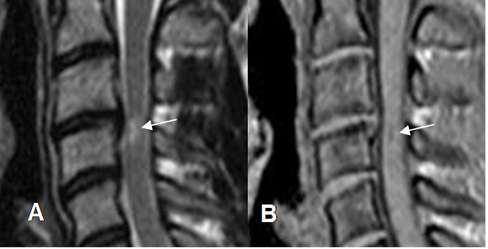

Fig 175. Lesión ligamentaria.

A: Rx lateral en flexión. Leve anterolistesis GI de C6, sobre C7.

B: RM sagital en STIR. Contusión del cuerpo vertebral, sin pérdida de altura. (Flecha gruesa). Hay cambios inflamatorios en los tejidos blandos prevertebrales (Flecha delgada), por esguince GI-II.